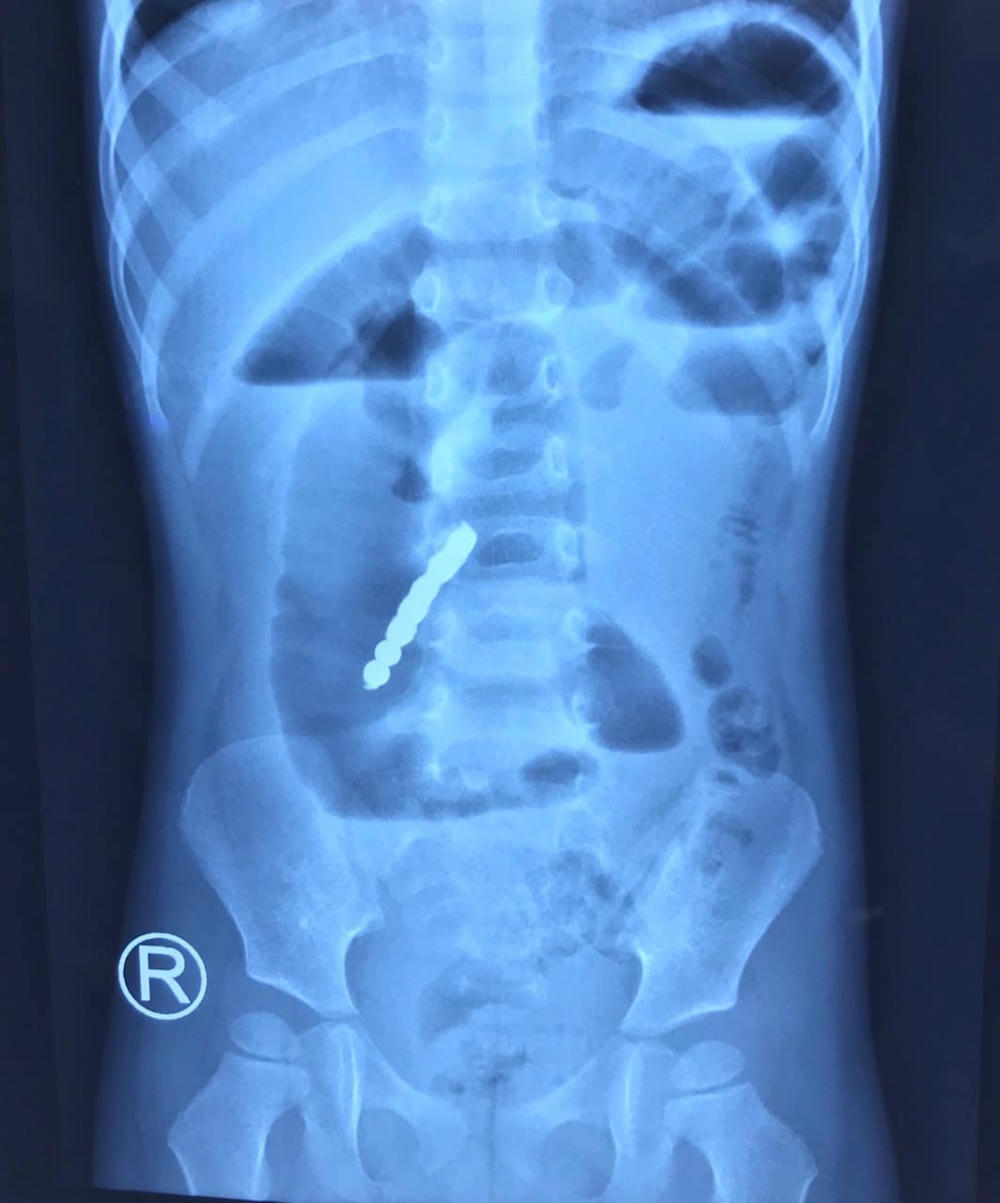

TS.BS Nguyễn Văn Linh, Trưởng Khoa ngoại Quốc Tế S, Bệnh viện Nhi Trung ương – người trực tiếp phẫu thuật cho bé T cho biết, ngày 4/3, trẻ nhập viện trong tình trạng đau bụng, nôn nhiều. Các bác sĩ đã chỉ định làm các xét nghiệm cận lâm sàng cho bệnh nhi. Kết quả chụp X-quang phát hiện hình ảnh tắc ruột kèm dị vật cản quang trong ổ bụng là 7 khối hình cầu dính thành chuỗi. Ngay lập tức trẻ được tiến hành mổ cấp cứu.

Hình ảnh dị vật của bệnh nhi qua chụp X-quang. (Ảnh: BVCC)

Ngày 4/3, trẻ nhập viện trong tình trạng đau bụng, nôn nhiều. Kết quả chụp X-quang phát hiện hình ảnh tắc ruột kèm dị vật cản quang trong ổ bụng là 7 khối hình cầu dính thành chuỗi.